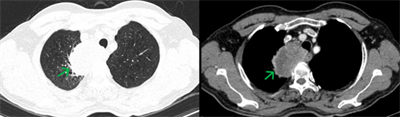

Ca lâm sàng: Điều trị đích bệnh nhân ung thư phổi không tế bào nhỏ giai đoạn muộn di căn nhiều cơ quan, tại Trung tâm Y học hạt nhân và Ung bướu –... Ngày đăng: 30/01/2026 Ung thư phổi là nguyên nhân hàng đầu gây tử vong do ung thư trên toàn thế giới. Trong đó, ung thư phổi không tế bào nhỏ (NSCLC) là thể thường gặp nhất, chiếm khoảng 85% các trường hợp [1]. Phần lớn...